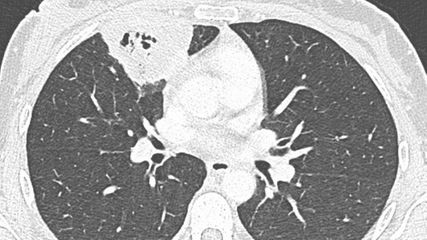

Der inhalierte Zigarettenrauch beschleunigt den Verlust der Lungenfunktion und führt somit zur COPD. Fletcher und Peto konnten bereits 1977 zeigen, dass ein Rauchstopp diesen beschleunigten Abfall aufhalten kann9 (Abb. 2). Dieser Zusammenhang kann in der Rauchstopp-Beratung als Motivation zum Rauchstopp verwendet werden: «Je früher, desto besser – lieber spät als nie!» Nikotin und weitere Bestandteile des Zigarettenrauchs führen zu einer Endotheldysfunktion, Vasokonstriktion, Gerinnungsaktivierung und begünstigen somit eine arterielle Hypertonie, Vaso-/Koronarsklerose und Ischämien. Rauchende (ab 20 Zigaretten/Tag) haben ein 4-fach erhöhtes Herzinfarktrisiko im Vergleich zu Nichtrauchenden.6 Das perioperative Risiko ist erhöht: Nikotin steigert die Stressantwort (Tachykardie, Hypertonie, Vasokonstriktion), CO ist proarrhythmogen und verringert das O2-Angebot im Gewebe. Die Wundheilung ist verzögert und die Infektanfälligkeit erhöht. Zudem haben Rauchende oft Vorerkrankungen (COPD, Hypertonie, koronare Herzkrankheit), welche das Operationsrisiko weiter erhöhen.11

Abb. 2: Die «Fletcher-Kurve» zeigt den natürlichen Verlauf der chronischen Atemwegsobstruktion in Abhängigkeit vom Rauchstatus (adaptiert nach Kotz et al., 2007)10